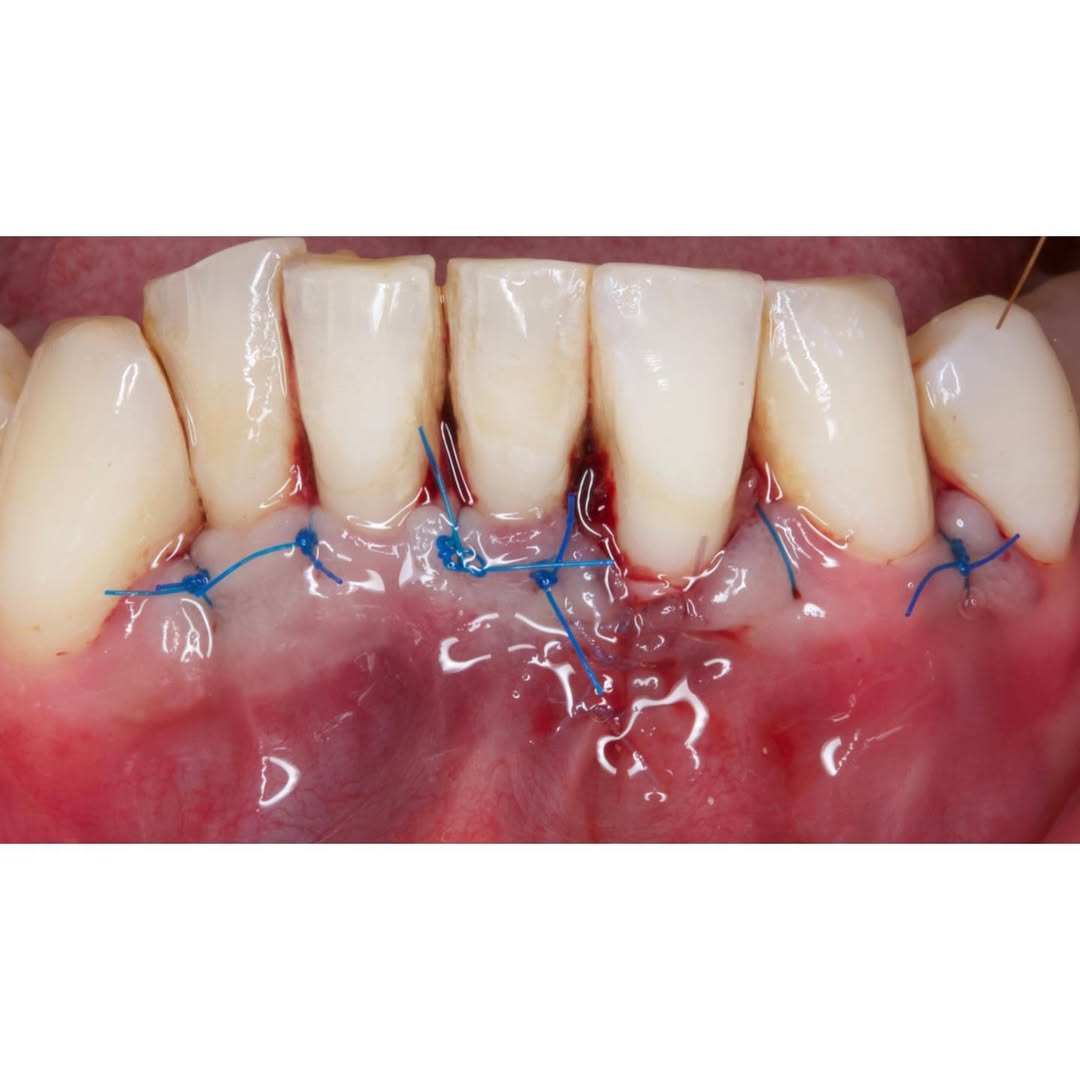

Durante una mañana, asistirás a una Cirugía Mucogingival de recubrimiento radicular de recesiones múltiples en IV y V sextante (36 a 43).

Gracias al uso del microscopio y a la proyección en tiempo real en pantalla, verás exactamente lo mismo que veo yo durante la cirugía, sin tener que estar

Aprende la planificación y técnica de la cirugía Mucogingival para el recubrimiento de recesiones y aumento de banda queratinizada en el sector anteroinferior

Una estancia clínica pensada para quienes quieran iniciarse o dar un paso más en el campo de la cirugía mucogingival. Durante esta experiencia tendrás la oportunidad de aprender en directo cómo se planifica y se lleva a cabo una cirugía mucogingival mediante técnica de Túnel.

La sesión